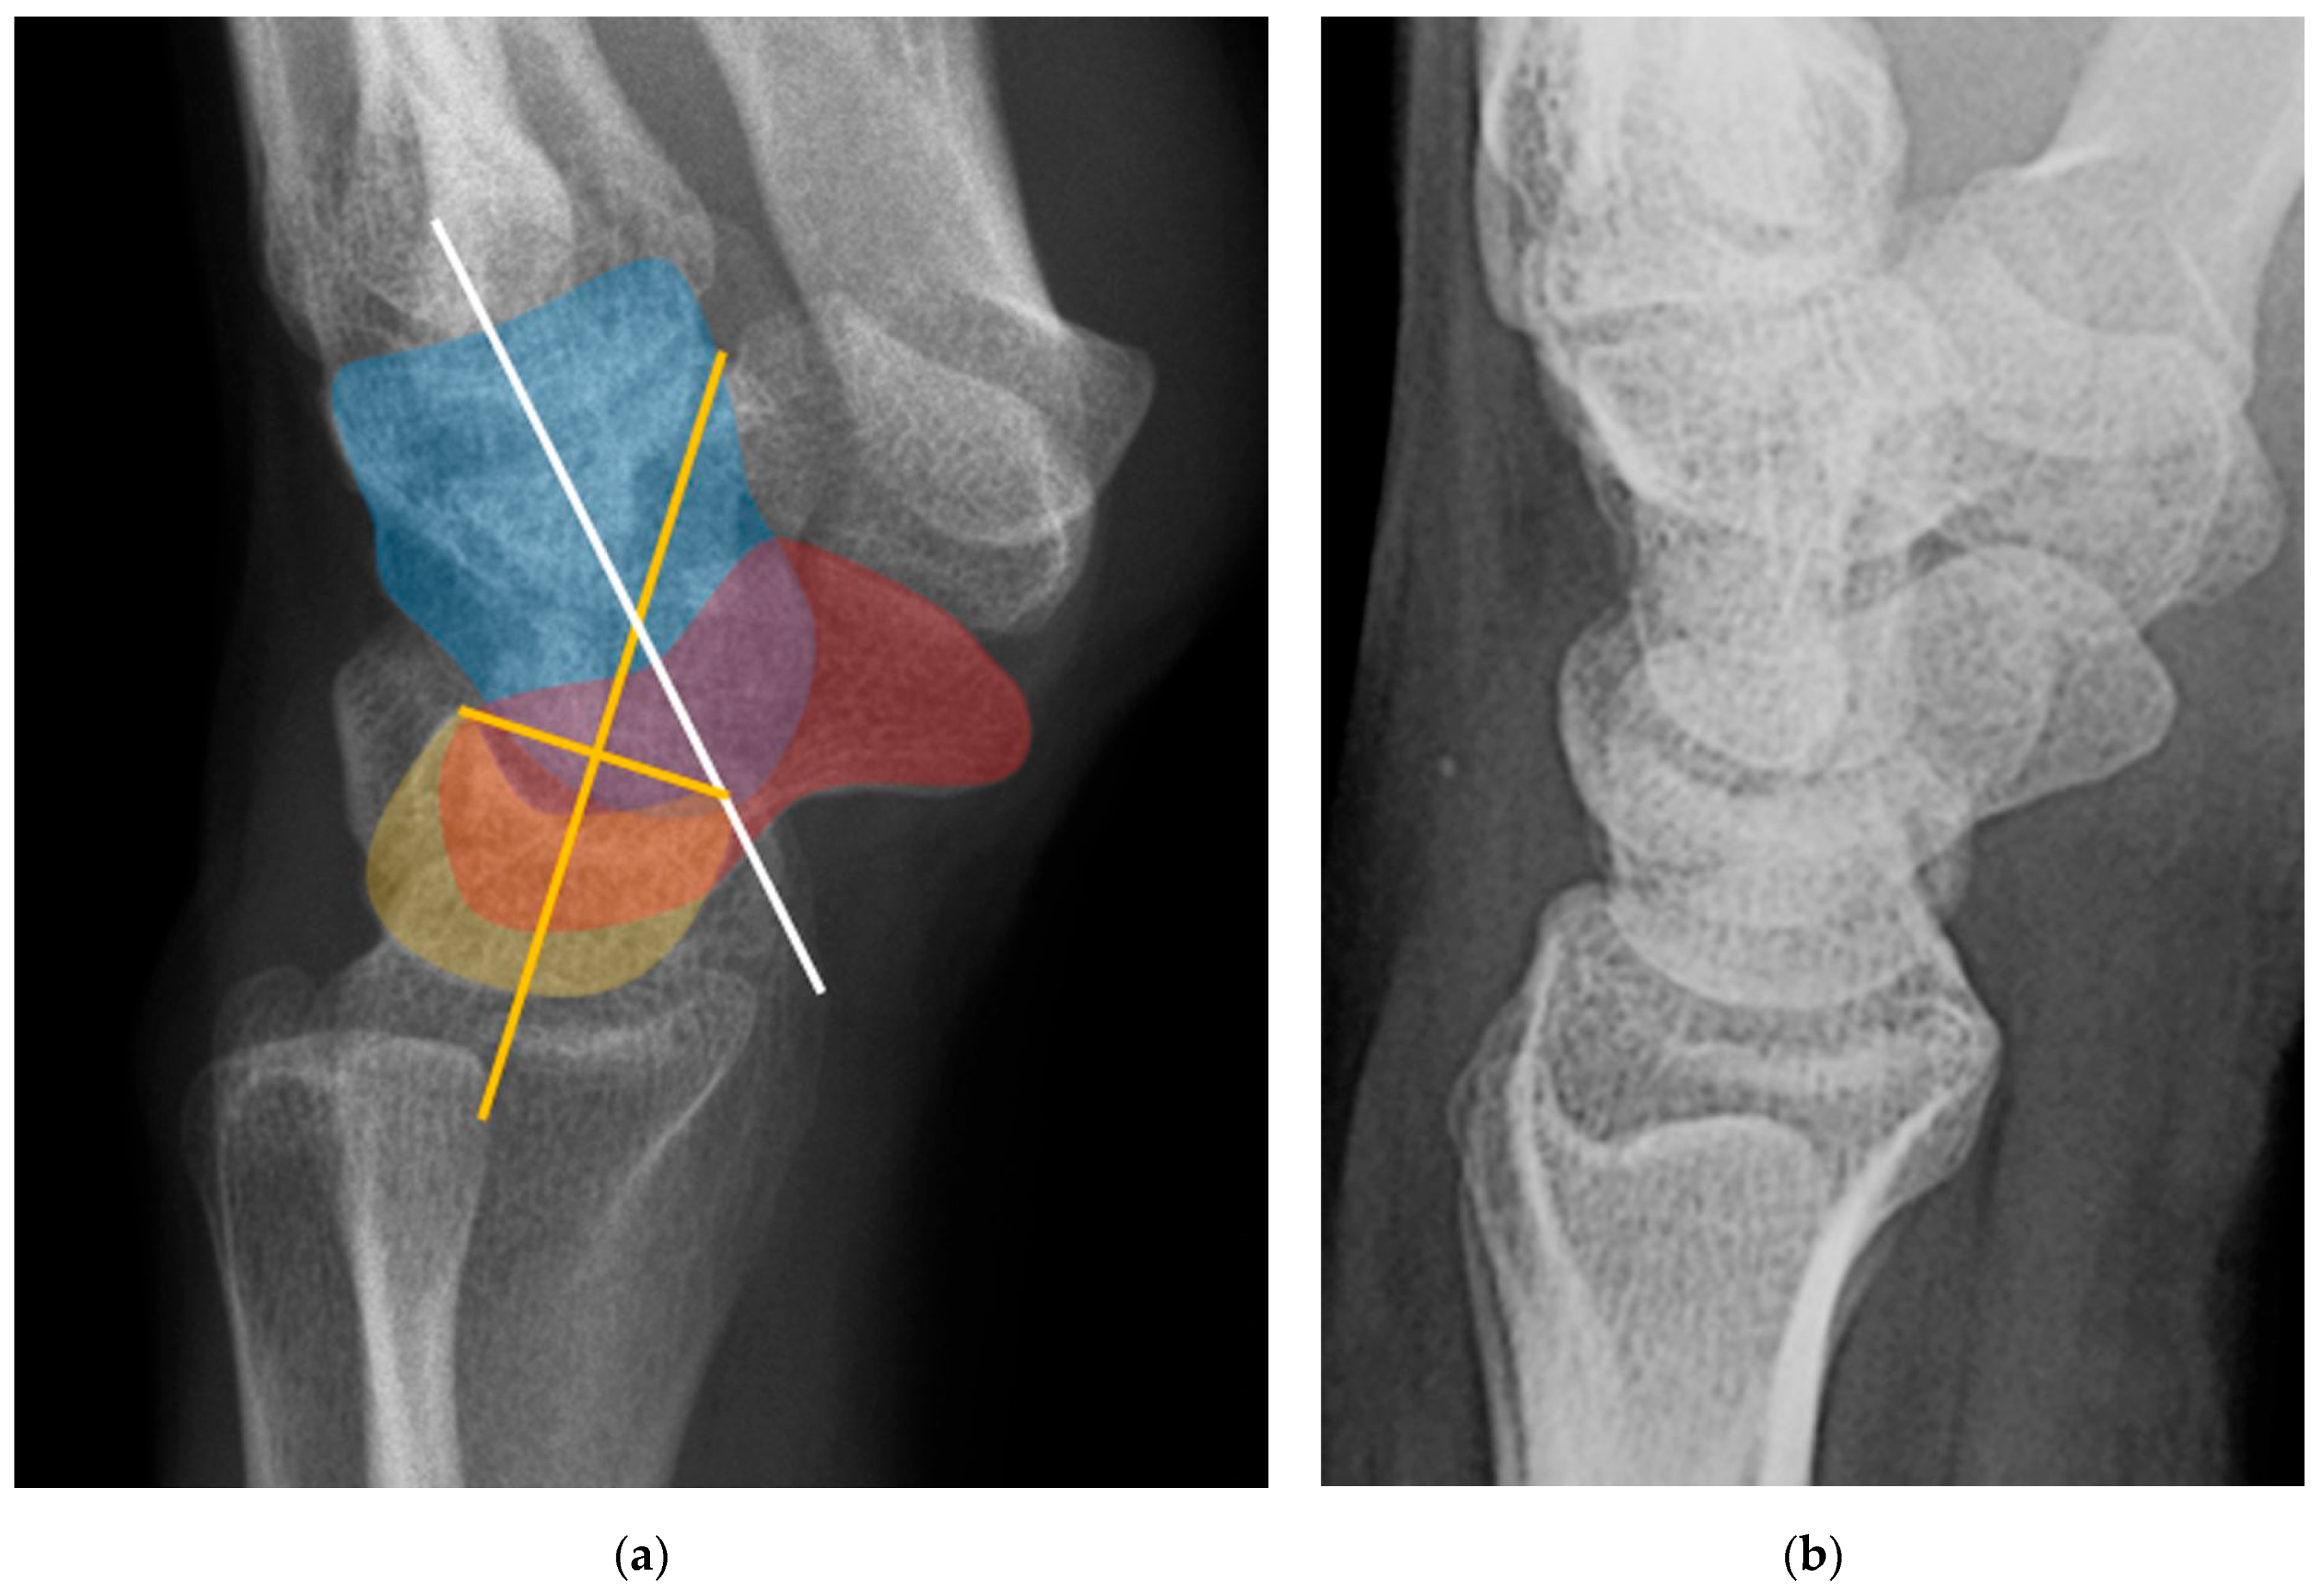

The scapholunate angle is formed between a line drawn along the axis or volar surface of the scaphoid and a line through the axis of the lunate, with the normal range being 30–60° (Figure 19) [3]. The capitolunate angle is formed between the lunate axis line and a line through the axis of the capitate, with a normal range of less than 30°, as these should be neutrally aligned (near 0°) in a normal wrist (Figure 19) [6,13].

Dorsal intercalated segment instability (DISI) occurs when there is disruption of the SLL [23]. The “intercalated segment” can be considered a bone or series of bones fixed in a passive position between other active motion segments [4]. Because the proximal carpal row including the scaphoid, lunate, and triquetrum has no tendinous attachments, its motion is solely passive, dependent on the forces applied through its surrounding constraints. DISI deformity begins when the SLL loses its integrity. Because the posterior fibers of SLL are the thickest, it is the main dorsal stabilizer restricting dorsal rotation of the lunate relative to the capitate, and the volar scaphoid rotation. The rupture of the SLL disrupts the stabilizing balance and results in this malalignment pattern. On a lateral radiograph of a normal wrist, the scapholunate angle measures between 30° and 60° as the scaphoid and lunate are both held upright by the SLL. After SLL rupture, the scapholunate angle widens to greater than 60° due to excessive volar rotation of the scaphoid relative to the lunate (Figure 32) often with eventual dorsal rotation of the lunate as well [8,21]. Management of DISI and acute tears of the SLL consists of surgical repair with suture anchors and temporary K-wire fixation.

Figure 32. (a) Lateral wrist radiograph with overlay showing excessive volar rotation of the scaphoid relative to the lunate, with an increased scapholunate angle to nearly 90°. The red line is drawn along the volar surface of the scaphoid while a yellow line is drawn through the lunate axis; (b) Normal lateral wrist radiograph for comparison. Capitate (blue), scaphoid (red), lunate (yellow).